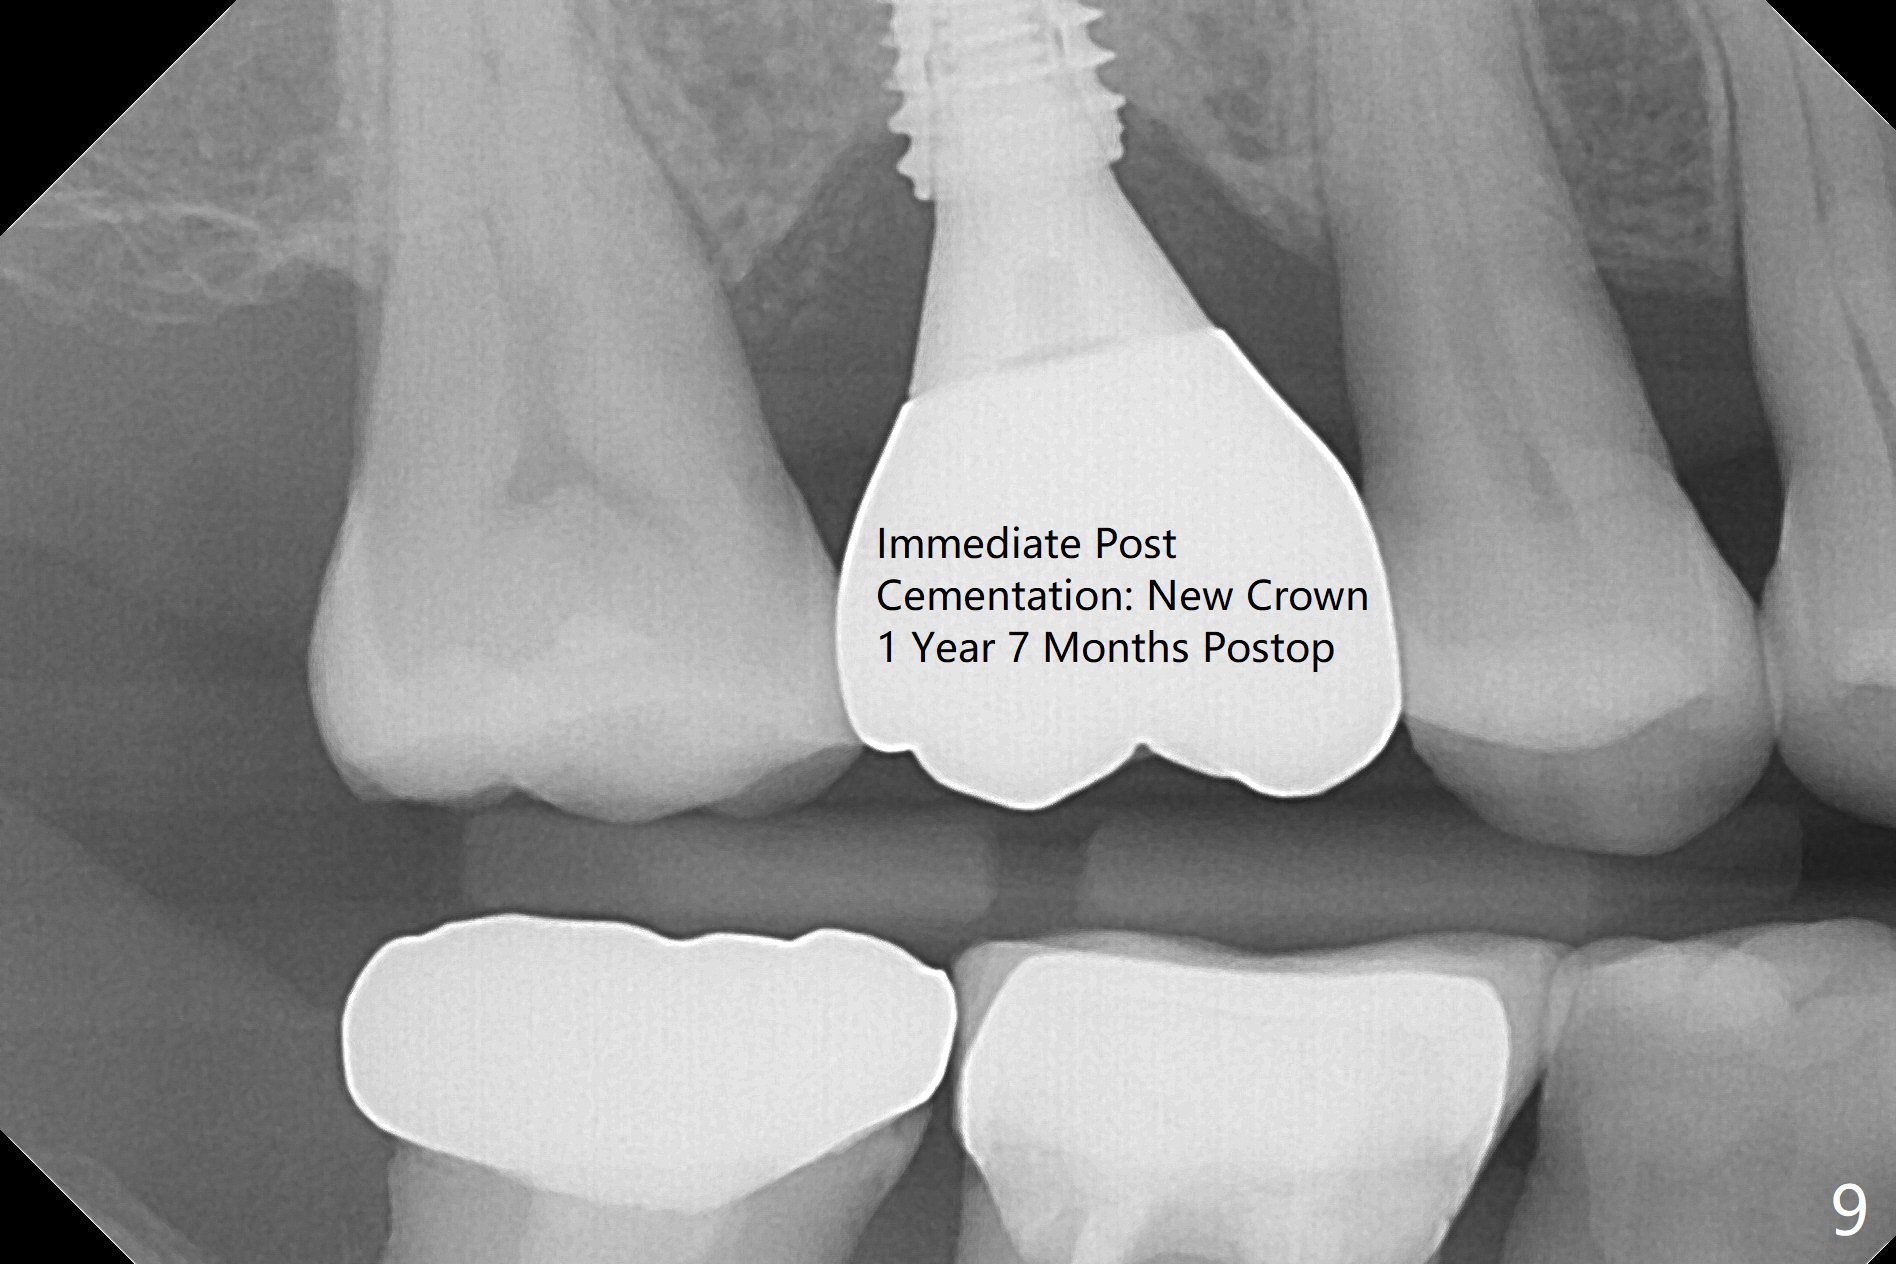

There is mild crestal bone loss 4.5 months postop (Fig.5).  When the patient returns for periodic exam and prophy 6 months post cementation, the crown is found to be loose, which is more likely associated with heavy mastication (long roots) and poor crown/implant ratio.  Since the distal contact is light, the case returns to lab.  PA taken following reseating the repaired abutment/crown shows crestal bone loss, which may be associated with the narrow ridge and/or the loose abutment.  The gingival cuff is less healthy (Fig.6).  The screw becomes loose again 4 months later.  When it is retightened, the distal proximal contact turns open (Fig.7 ^).  The crown appears to turn with the underlying abutment (Fig.8).  After breaking proximal contacts, the crown/abutment is retightened and pick up impression is taken.  It is likely that the abutment was not seated right when abutment-level impression was taken.  The crown table is slightly oversized (Fig.8). Three months later, the screw becomes loose for the 3rd time (unilateral mastication, pain at #19 without RCT).  The abutment hex is not worn.  The crown is removed and the abutment is reseated and torqued 30 Ncm.  Impression is taken for new crown.  The latter is cemented without removing the abutment (Fig.9 (note bone loss)).  In fact the crown/abutment should have been torqued with screw driver buried in place!